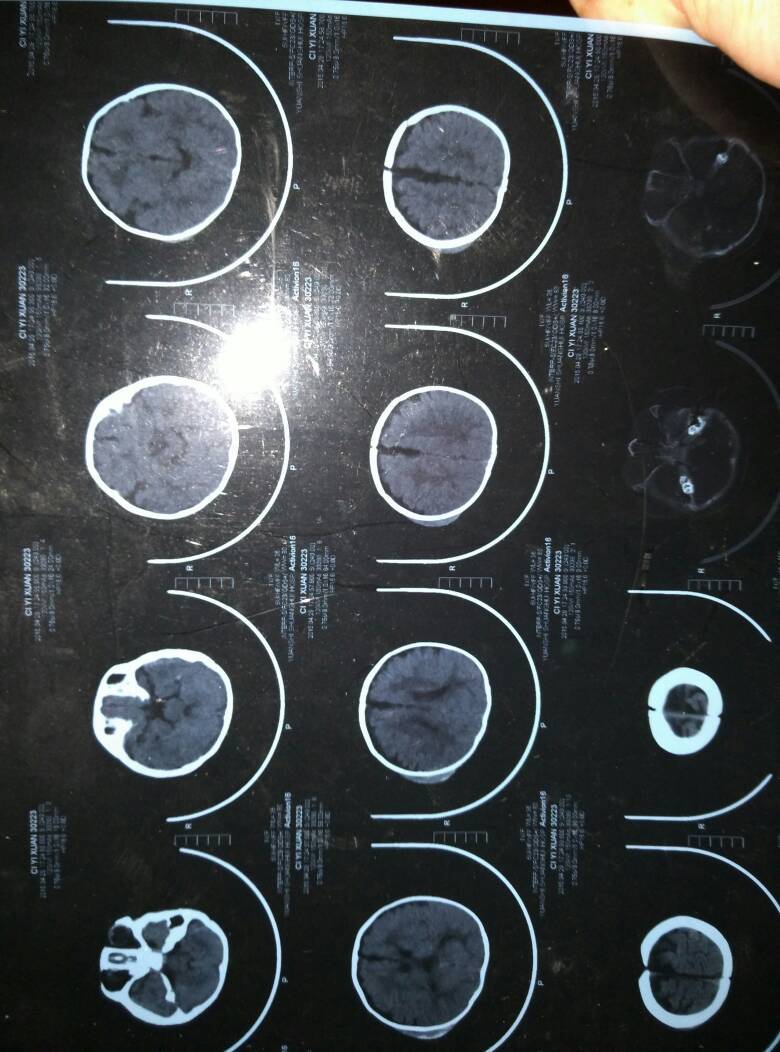

六个月宝宝头上可能碰到起个包,查CT意外发现轻度脑积水,医生开了一个月口服液(脑蛋白水解物口服液),说吃完不放心可以再复查次CT(好像说到2周左右复查,忘了)。我想问下宝宝这病严重吗,吃这药管用吗,还用复查吗